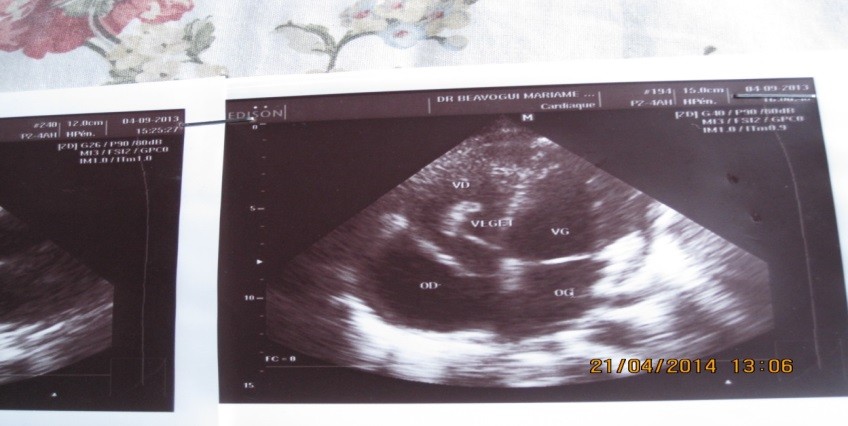

L’échocardiographie transthoracique montrait une grosse végétation mobile, appendue à l’extrémité de la valve septale de la valvule tricuspide, avec éversion et prolapsus de la valve antérieure dans l’oreillette droite en systole. Les cavités cardiaques droites étaient dilatées. La fonction systolique du ventricule droit était conservée. On notait une insuffisance tricuspidienne modérée avec une hypertension artérielle pulmonaire (PAPS=46 mmHg) Cf figure 1.

Figure 1 : Echocardiographie 2D, coupe apicale 4 cavités montrant une végétation

Sur la valve septale de la tricuspide et une éversion de la valve antérieure